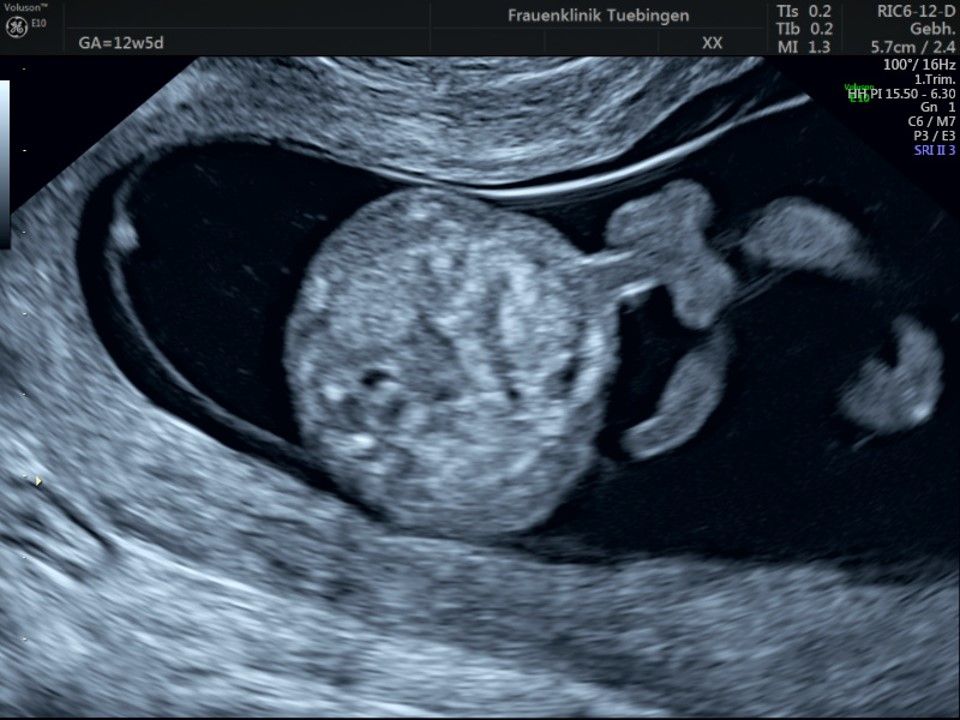

Im Rahmen des Ersttrimester-Screenings untersuchen wir die Organe des Feten mittels Ultraschall. Dabei machen wir auch gerne ein Bild für Sie.

Obwohl der Fet zu diesem Zeitpunkt erst zwischen 5 und 8cm groß ist, lassen sich bereits etwa die Hälfte aller schwerwiegenden Fehlbildungen erkennen bzw. ausschließen. Sollten wir eine Auffälligkeit sehen, werden wir mit Ihnen den Befund und das weitere Vorgehen ausführlich besprechen.

Fetale Anatomie